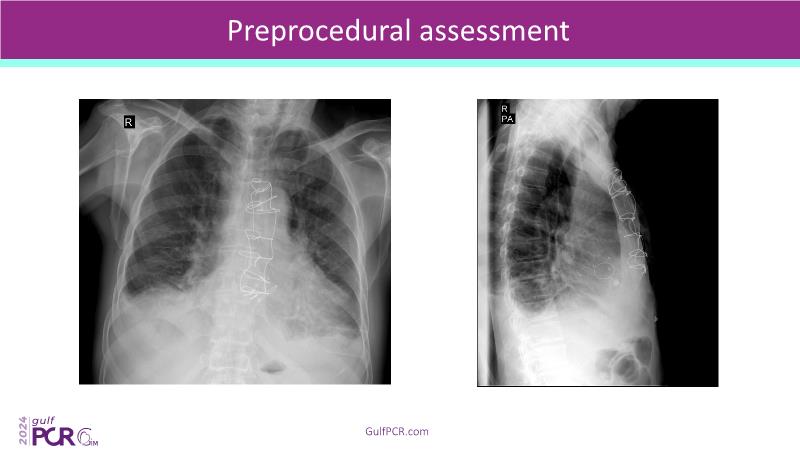

Stay ahead in TAVI innovation by exploring the advanced balloon-expandable Myval THV series. This session highlights the latest clinical data, optimal sizing and implantation techniques, and valuable real-world insights, including long-term follow-up results.

- To understand the best practices for Myval sizing and implantation technique for best outcomes